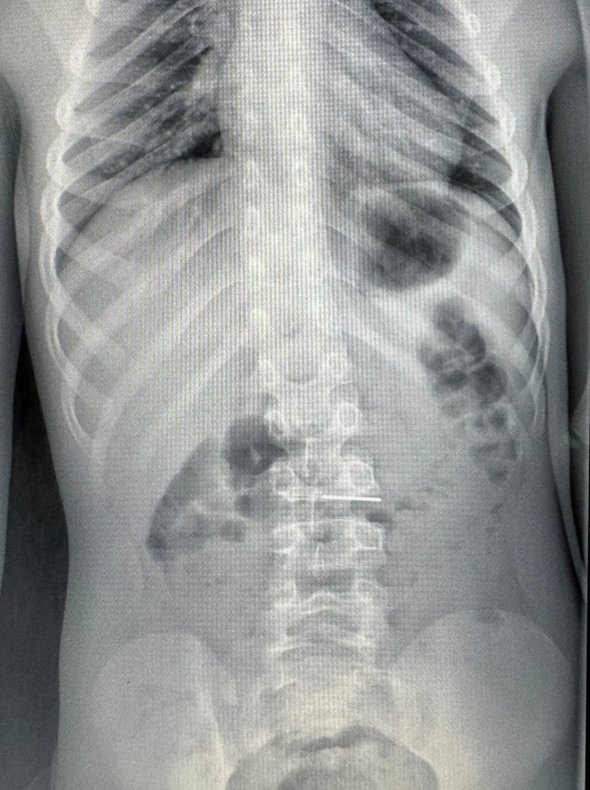

По словам медиков, дома мальчик пожаловался родителям на сильные боли в животе, тогда отец повез сына в больницу. Рентген и КТ показали наличие в теле инородного предмета, похожего на иглу. Результаты подтвердили наличие иголки в верхних отделах ЖКТ. Игла зафиксировалась острым концом в слизистой оболочке двенадцатиперстной кишки. Мальчику выполнили экстренную эндоскопическую операцию.

фото: vk.com/roshal_kids